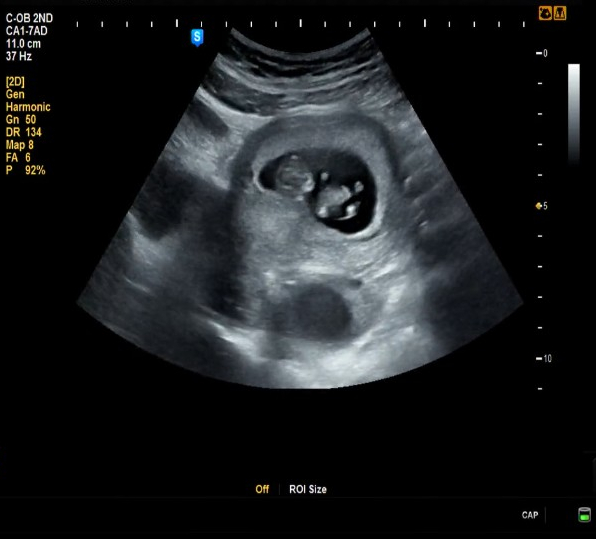

2023.08.09 (9W 6D) 활발한 젤리곰 띠용이♡

세번째 만나러 왔는데 배에 초음파기를 갖다댔더니 성냥개비 대가리만한 팔다리를 흔들며 춤을 추는 띠용이...